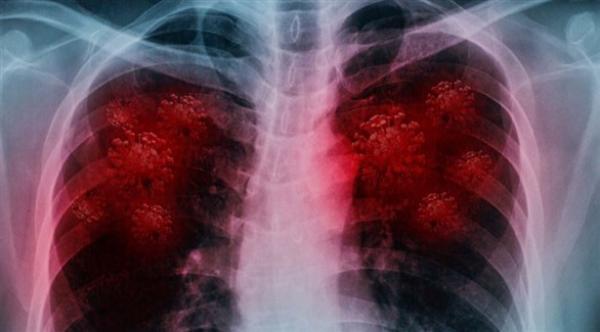

وتوصل فريق الدراسة إلى أن المعادلة الخوارزمية للذكاء الاصطناعي يمكن تدريبها لرصد بؤر الإصابة بفيروس كورونا في صور الاشعة بدرجة دقة تبلغ 90%، كما يمكنها اكتشاف الحالات الإيجابية بنسبة 84% والحالات السلبية بنسبة 93%.

ومن أجل إجراء التجربة، تم تدريب منظومة الذكاء الاصطناعي على اكتشاف بؤر الإصابة بفيروس كورونا في صور الأشعة المقطعية الخاصة بـ1280 مريضاً من الصين واليابان وإيطاليا، ثم تم اختبارها على صور أشعة 1337 مريضاً بأمراض رئة تتنوع ما بين فيروس كورونا والالتهاب الرئوي العادي وسرطان الرئة.

وقال باجسي: "لقد أثبتنا أن منظومات الذكاء الاصطناعي القوية يمكنها اكتشاف حالات الإصابة بفيروس كورونا المستجد بنسبة دقة تصل إلى 90%".